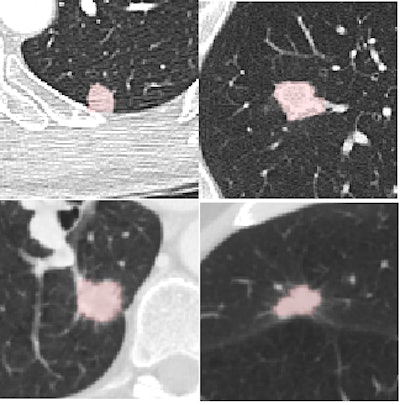

The study used CAD to analyze CT scans of the 108 LIDC subjects acquired with slice thicknesses and reconstruction intervals ranging from 0.5 mm to 3.0 mm (mean 2.1 mm), mAs ranging from 75 to 300, and kVp ranging from 120 to 140. The investigators chose a wide variety of nodules types from the LIDC database to show the range of nodule types detected in practice. Samples varied in size (from small to large), shape (including round, irregular, speculated, and cavitated), and connectivity from isolate to contacting vessels and pleura. Scanner manufacturers included GE Healthcare, Siemens Healthcare, and Toshiba Medical Systems.

From the LIDC database of nodules analyzed by the CAD, only findings considered nodules by a majority of the four radiologist readers who originally evaluated the nodule were included for analysis by CAD. Findings were rated true positive, false negative, or false positive.